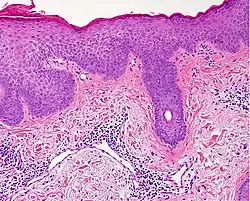

Main conditions[2] Characteristics Micrograph Photograph

Generally/Not otherwise specified Typical findings:[2]

• In the papillary dermis: a confluent, band-like, dense inflammation of mainly small lymphocytes and a few histiocytes, along or hugging the dermoepidermal junction.

• Often vacuolar degeneration of basal keratinocytes and apoptotic bodies (colloid or Civatte bodies).